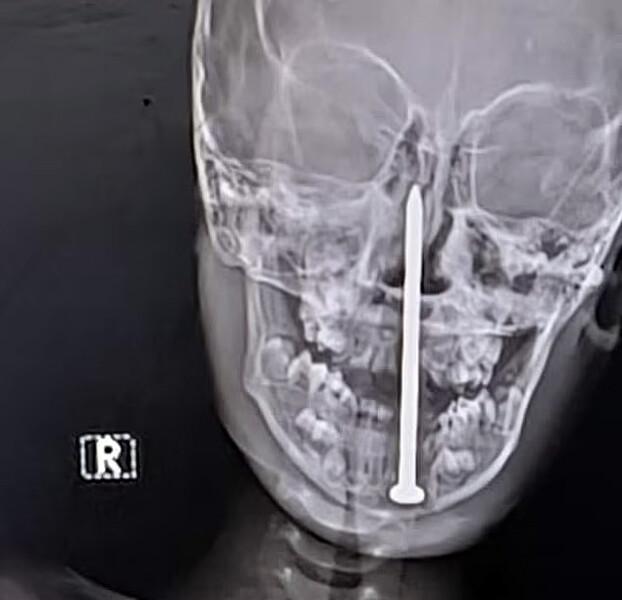

В штате Раджастан семилетнему мальчику потребовалось сложное нейрохирургическое вмешательство. Медики успешно извлекли из его головного мозга семисантиметровый гвоздь, сообщает Daily Mail.

Согласно информации, полученной от местных источников, несчастный случай произошел во время игры ребенка возле стройки. Он споткнулся и упал лицом прямо на гвоздь. Мальчика оперативно доставили в больницу Джайпура, где томография показала, что инородное тело проникло почти на пять сантиметров вглубь мозга.

Команда хирургов, возглавляемая доктором Санкетом Шармой, провела операцию, длившуюся более четырех часов, чтобы извлечь гвоздь. Медики отметили, что мальчику повезло, так как были задеты только лобные доли, отвечающие преимущественно за познавательные процессы, а не жизненно важные структуры.

После хирургического вмешательства состояние ребенка стабильное, однако он находится в реанимации под пристальным наблюдением врачей.